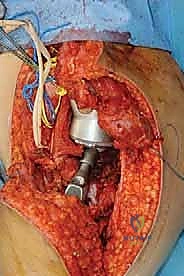

تعتمد جراحة إنقاذ الأطراف الناجحة على ثلاث مراحل مترابطة، يتم إجراؤها بالتسلسل وبدقة مطلقة داخل غرفة العمليات المجهزة بأحدث التقنيات تحت إشراف الأستاذ الدكتور محمد هطيف:

1. استئصال الورم بهوامش أورام مناسبة (Tumor Resection)

هذا أمر غير قابل للتفاوض. الهدف الأساسي دائماً هو الإزالة الكاملة للورم بكتلة واحدة (En bloc resection) مع تغليفه بطبقة من الأنسجة السليمة (العضلات والدهون) لضمان عدم تسرب أي خلية سرطانية إلى الجرح.

يستخدم الدكتور هطيف تقنيات الجراحة الميكروسكوبية لفصل الأوعية الدموية والأعصاب الرئيسية عن الورم بعناية فائقة لإنقاذها.

2. إعادة بناء وتثبيت العظم والمفاصل المصابة (Reconstruction)

بمجرد إزالة الورم والفراغ العظمي الكبير، يبدأ بناء الطرف الجديد. هنا يأتي دور أنظمة الأطراف الاصطناعية الداخلية.

* يتم تحضير القنوات النخاعية للعظام المتبقية.

* يتم إدخال سيقان الغرسة (إما باستخدام الأسمنت العظمي الطبي للتثبيت الفوري، أو سيقان غير أسمنتية مغطاة بمواد مسامية تسمح للعظم الطبيعي بالنمو داخلها والالتحام بها).

* يتم تجميع القطع المعيارية لتعويض الطول الدقيق للعظم المفقود.

* يتم ربط آلية المفصل الجديد (مثلاً، مفصل ركبة مفصلي Hinge joint يوفر الاستقرار الكامل).

3. استعادة الغلاف النسيجي الرخو (Soft Tissue Coverage)

أمر بالغ الأهمية لحماية الزرعة المعدنية، ومنع العدوى، وتمكين استعادة الوظيفة. لا يمكن ترك المعدن تحت الجلد مباشرة.

يقوم الدكتور هطيف بنقل عضلات من مناطق مجاورة (مثل عضلة الساق التوأمية Gastrocnemius flap في جراحات الركبة) لتغطية المفصل الصناعي بالكامل، وتوفير تروية دموية ممتازة للمنطقة، وإعادة ربط الأوتار لضمان قدرة المريض على تحريك المفصل.